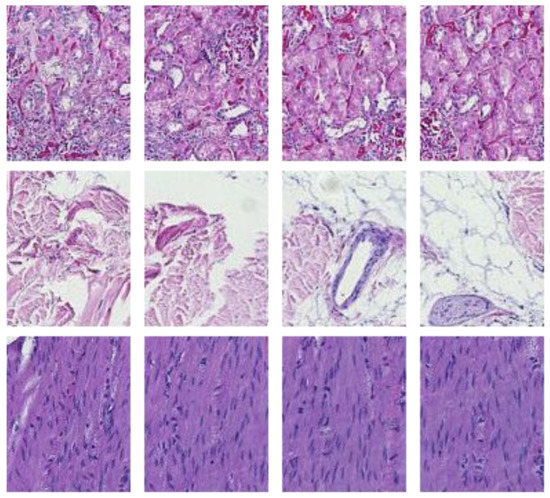

The preprocessing stage began with 66 WSI scans; we digitally cropped one region of interest (ROI) of size 1440 × 904 pixels for each tissue type in each slide. This resulted in three sets of images of 66 ROIs each, one set for the kidney, one for the skin, and one for the colon tissue. Cropping was used to minimize the presence of the non-tissue-related background, such as dust, hair, fibers, and other artifacts from previous preprocessing steps. The selected region coordinates were approximately the same within each tissue type. Each ROI was localized to cover an approximately sufficient area in each tissue type. Figure 3 shows samples of such ROIs for each tissue type amongst nine randomly chosen laboratories (three laboratories per tissue type).

Figure 3.

For illustration purposes, three ROIs from three laboratories per tissue type (column-wise). The first column is skin, the second column is kidney, and the last column is colon.